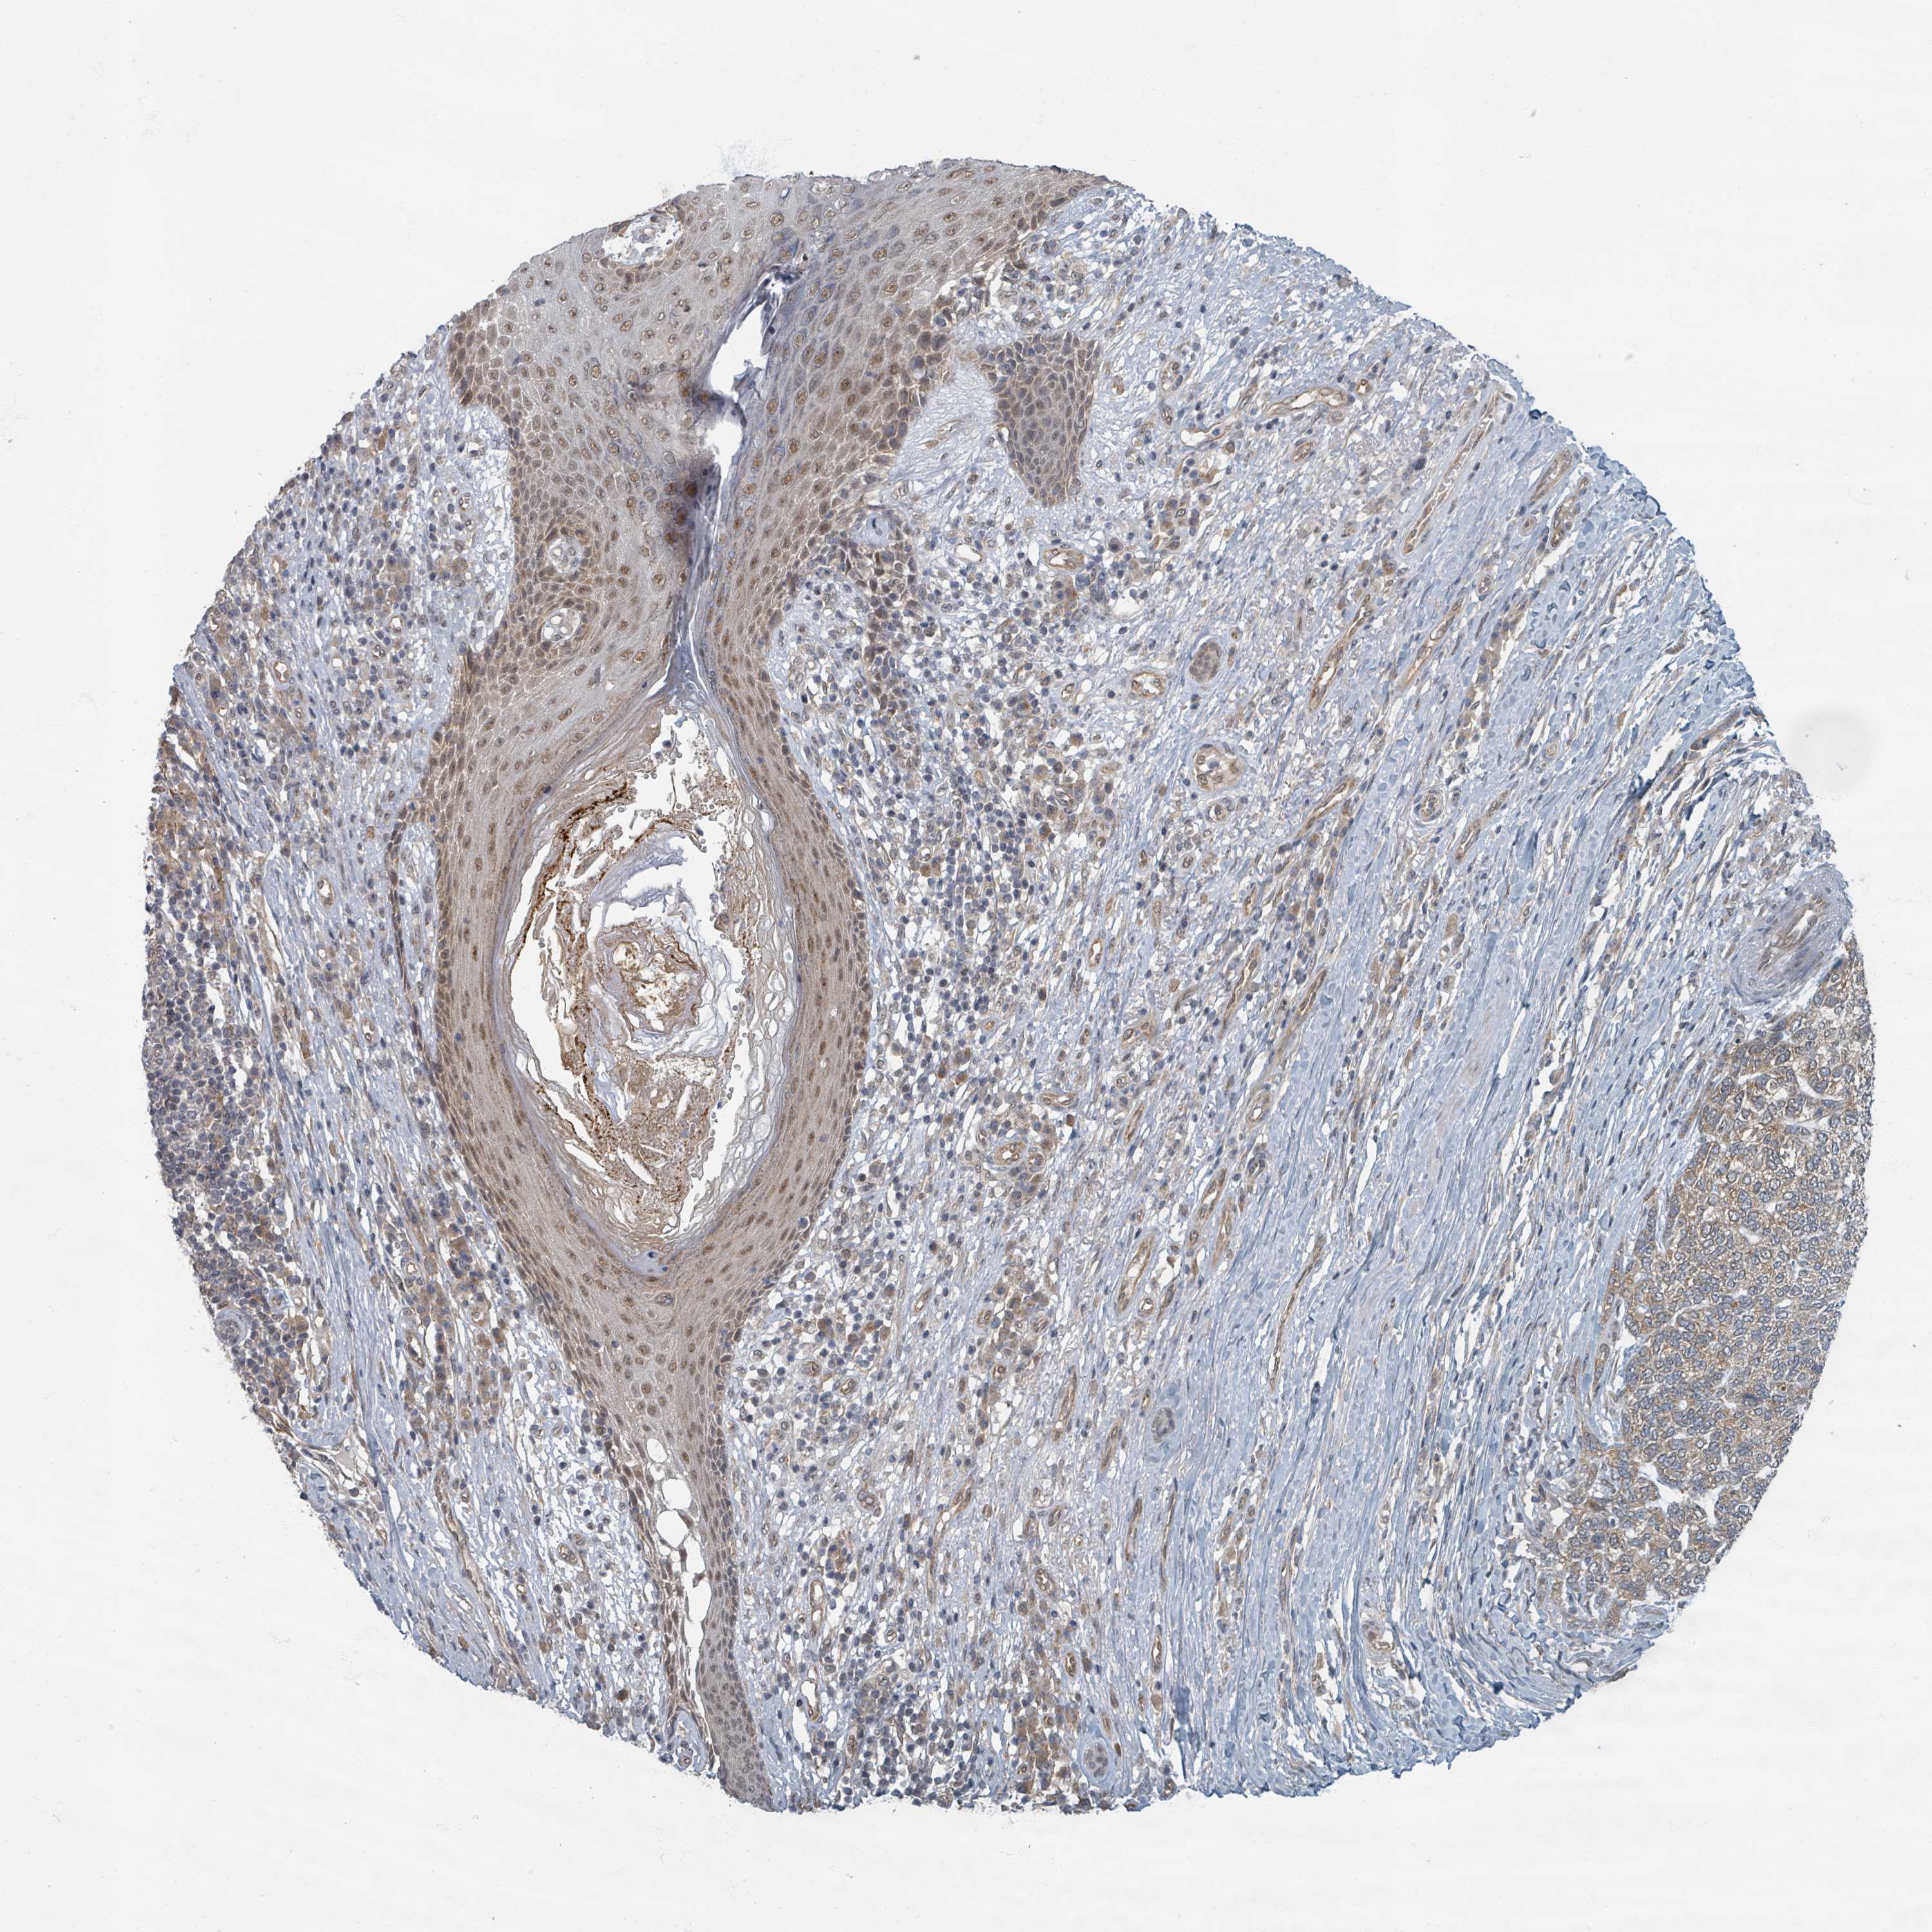

SKIN CANCER - Protein expressioni

A mouse-over function shows sample information and annotation data. Click on an image to view it in a full screen mode. Samples can be filtered based on level of antibody staining by selecting one or several of the following categories: high, medium, low and not detected. The assay and annotation is described here.

Antibody staining in the annotated cell types in the current human tissue is reported as not detected, low, medium, or high, based on conventional immunohistochemistry profiling in selected tissues. This score is based on the combination of the staining intensity and fraction of stained cells.

Each image is clickable and will lead to virtual microscopy that enables deeper exploration of all samples and also displays staining intensity scores, fraction scores and subcellular localization as well as patient and tissue information for each sample.

Antibody HPA052175

Basal cell carcinoma

Squamous cell carcinoma, NOS

Squamous cell carcinoma, metastatic, NOS